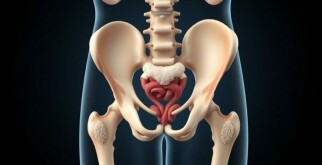

Case Study: Una paciente embarazada con dolor abdominal derecho — Un viaje clínico entre el suspenso y la decisión